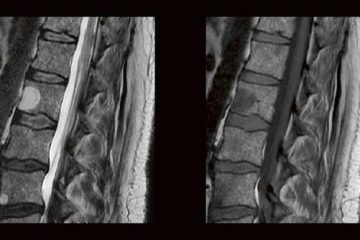

Die technischen Fortschritte bei der Entwicklung neuer Ultraschallgeräte (hochfrequente Ultrabreitband-Linearschallköpfe, Matrixsonden, Verfahren zur Beurteilung der Mikrovaskularisation) sowie Verbesserungen bei der Darstellung von Punktionsnadeln haben in den Gebietender Neurologie, Schmerztherapie, Unfallchirurgie/Orthopädie und Anästhesiologie in den letzten Jahren die Anwendungsbereiche der hochfrequenten Sonographie erheblich erweitert. Unser Anwenderseminar, welches zum 5. Mal ausgerichtet wird, Weiterlesen…